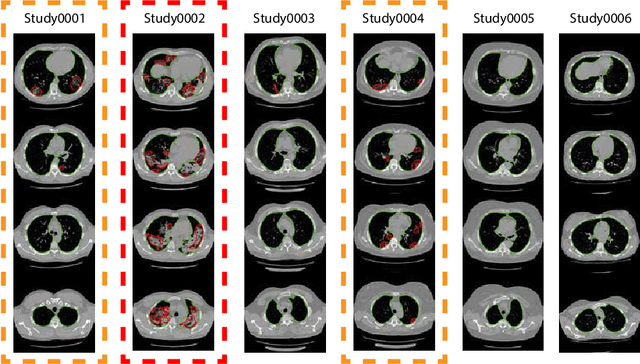

Abstract:The current COVID-19 pandemic overloads healthcare systems, including radiology departments. Though several deep learning approaches were developed to assist in CT analysis, nobody considered study triage directly as a computer science problem. We describe two basic setups: Identification of COVID-19 to prioritize studies of potentially infected patients to isolate them as early as possible; Severity quantification to highlight studies of severe patients and direct them to a hospital or provide emergency medical care. We formalize these tasks as binary classification and estimation of affected lung percentage. Though similar problems were well-studied separately, we show that existing methods provide reasonable quality only for one of these setups. To consolidate both triage approaches, we employ a multitask learning and propose a convolutional neural network to combine all available labels within a single model. We train our model on approximately 2000 publicly available CT studies and test it with a carefully designed set consisting of 33 COVID patients, 32 healthy patients, and 36 patients with other lung pathologies to emulate a typical patient flow in an out-patient hospital. The developed model achieved 0.951 ROC AUC for Identification of COVID-19 and 0.98 Spearman Correlation for Severity quantification. We release all the code and create a public leaderboard, where other community members can test their models on our dataset.